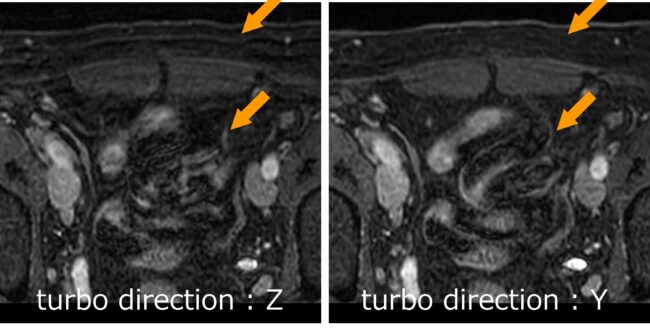

落ちムラ無し!!B-TFEでもSTIR!